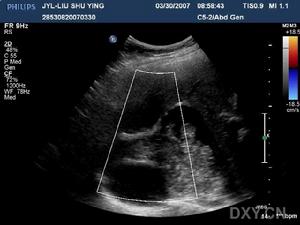

2.超音波檢查可發現膿腫部位有典型的液性回聲暗區或膿腫內液平面。該檢查除能協助臨床診斷外,還可以幫助了解膿腔的部位、大小及距體表的深度,以便確定膿腫的最佳穿刺點和進針方向與深度,或為手術引流提供入路選擇。但超聲對小於1cm的多發性肝膿腫,往往難以發現,臨床診斷時應予注意。從超聲學的角度,還需要與其他囊性病變鑑別。一般情況下,肝囊腫的囊壁整齊清晰,囊內密度均勻一致。而肝膿腫的腔壁不規則,界限不清楚,腔內常含有多個回聲區。